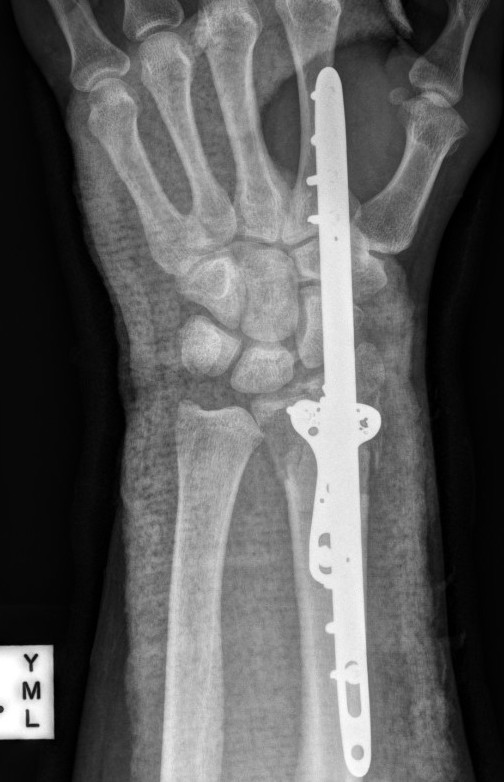

ORIF with locking plates

Advantages

Accurate restoration of intra-articular anatomy

Stable fixation with early mobilisation

Fragment specific plates

| Volar locking plates | Volar rim plates | Radial styloid plates |

Volar locking plate technique

AO surgery modified Henry to distal forearm

Vumedi volar locking plate distal radius

Bed of FCR approach

- incision over FCR and mobilize ulnarly

- divide fascia in bed of FCR and retract radial artery laterally

- L shaped released of pronator quadratus

- cannot make volar capsulotomy - divides radiocarpal ligaments and causes instability

- elevate 1st extensor compartment (APL / EPB)

- release brachioradialis from radial styloid

Reduce fragments and temporarily stabilize with K wires

- apply volar plate with screw fixation in scaphoid and lunate fragments

- ensure not beyond watershed line to avoid flexor tendon irritation / rupture

- engage dorsal cortex but not too long to prevent EPL rupture

- on lateral, raise hand 30o to view joint

- +/- radial styloid plate if required